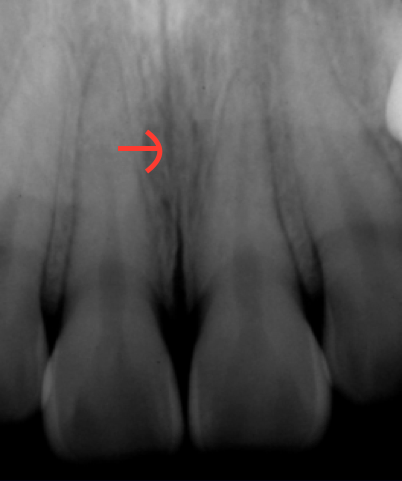

Sinus

Hollow space, cavity, or recess in bone; Example is maxillary sinus.